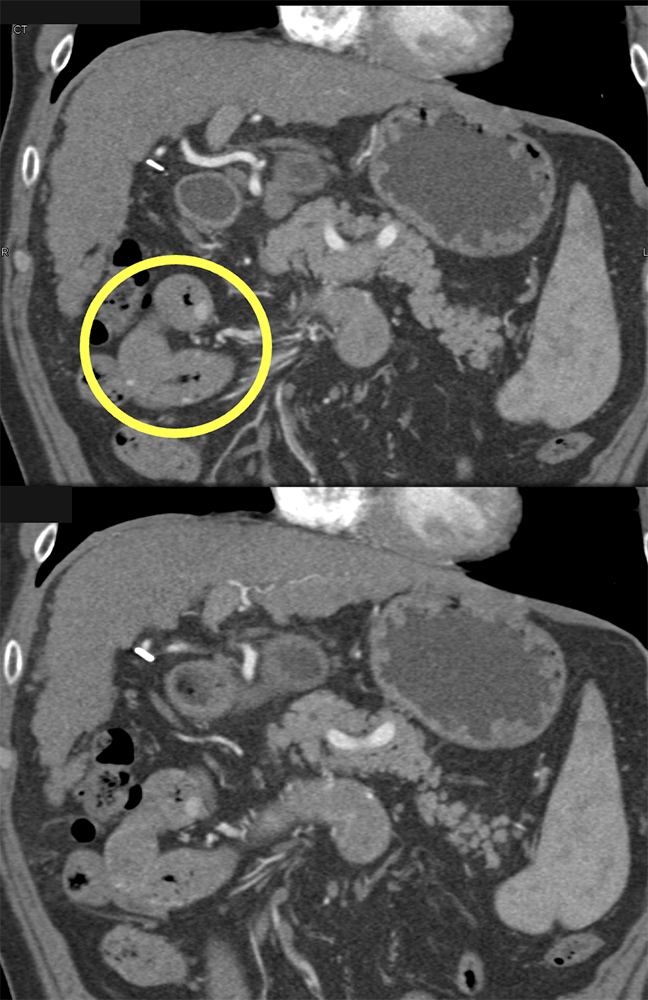

GIST Tumor Jejunum as the Cause of GI Bleeding ![]() |

![]() |

GI Bleed ![]() |